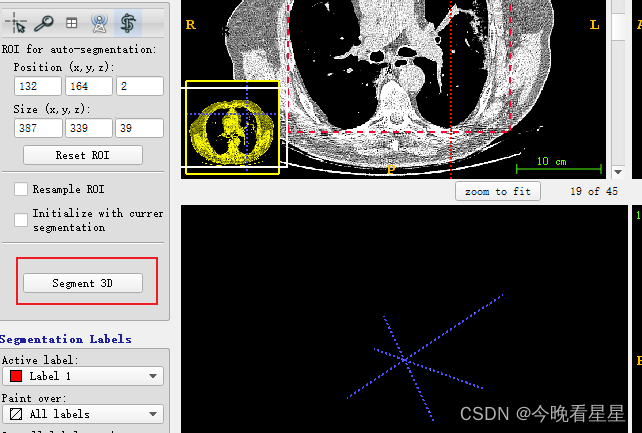

-

使用矩形框进行框选,并在多个视图中确定区域

-

在左侧进行3D分割

- 看第二个视图, 蓝色为丢弃区域,白色为选择的区域,进行CT阈值的调节,来选择想要的部分。参数调整完毕后,选择next进行下一步操作